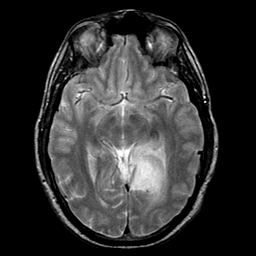

glioma overlay -- Slice #12

[Home][Help][Clinical] Slice 12